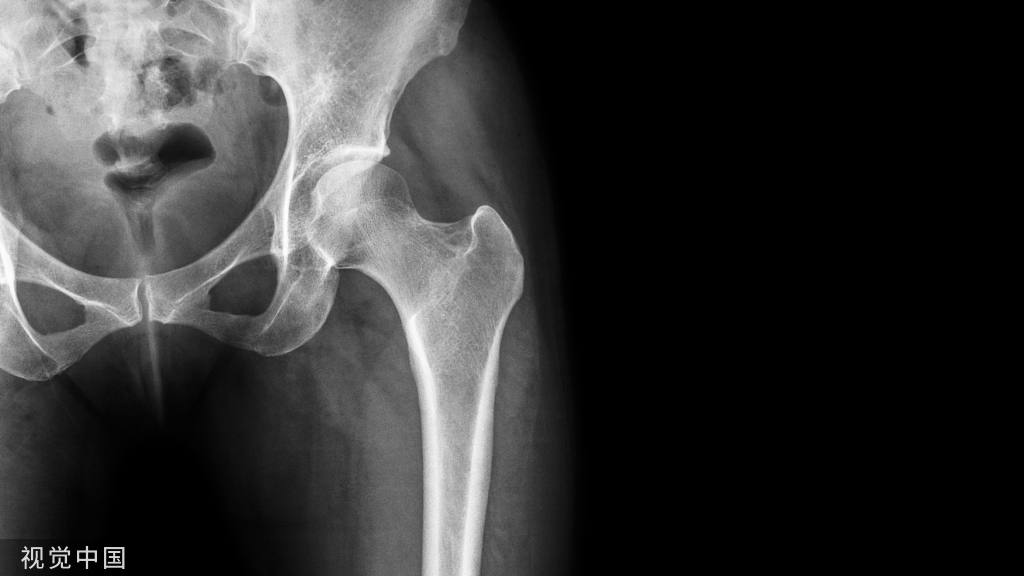

临床诊断冠状突骨折时常采用CT、X线片以及三维重建这三种影像学检查。

X线片检查冠状突骨折时相较于CT检查,其整体性与方便性较高,检查人员能够直观的看到患者冠状突骨折以及周围组织损伤的情况,方便医生作进一步的诊断。但是X线检查仍存在一些不足,当冠状突的体积较小时,如果有重叠遮挡的情况,通过X线很容易发生漏诊的情况;如果患者冠状突骨折伴有其他肘关节组织损伤,X线不容易辨别骨折块的来源;X线无法实现全方位观察关节面,使得检查人员能够观察的角度受限。